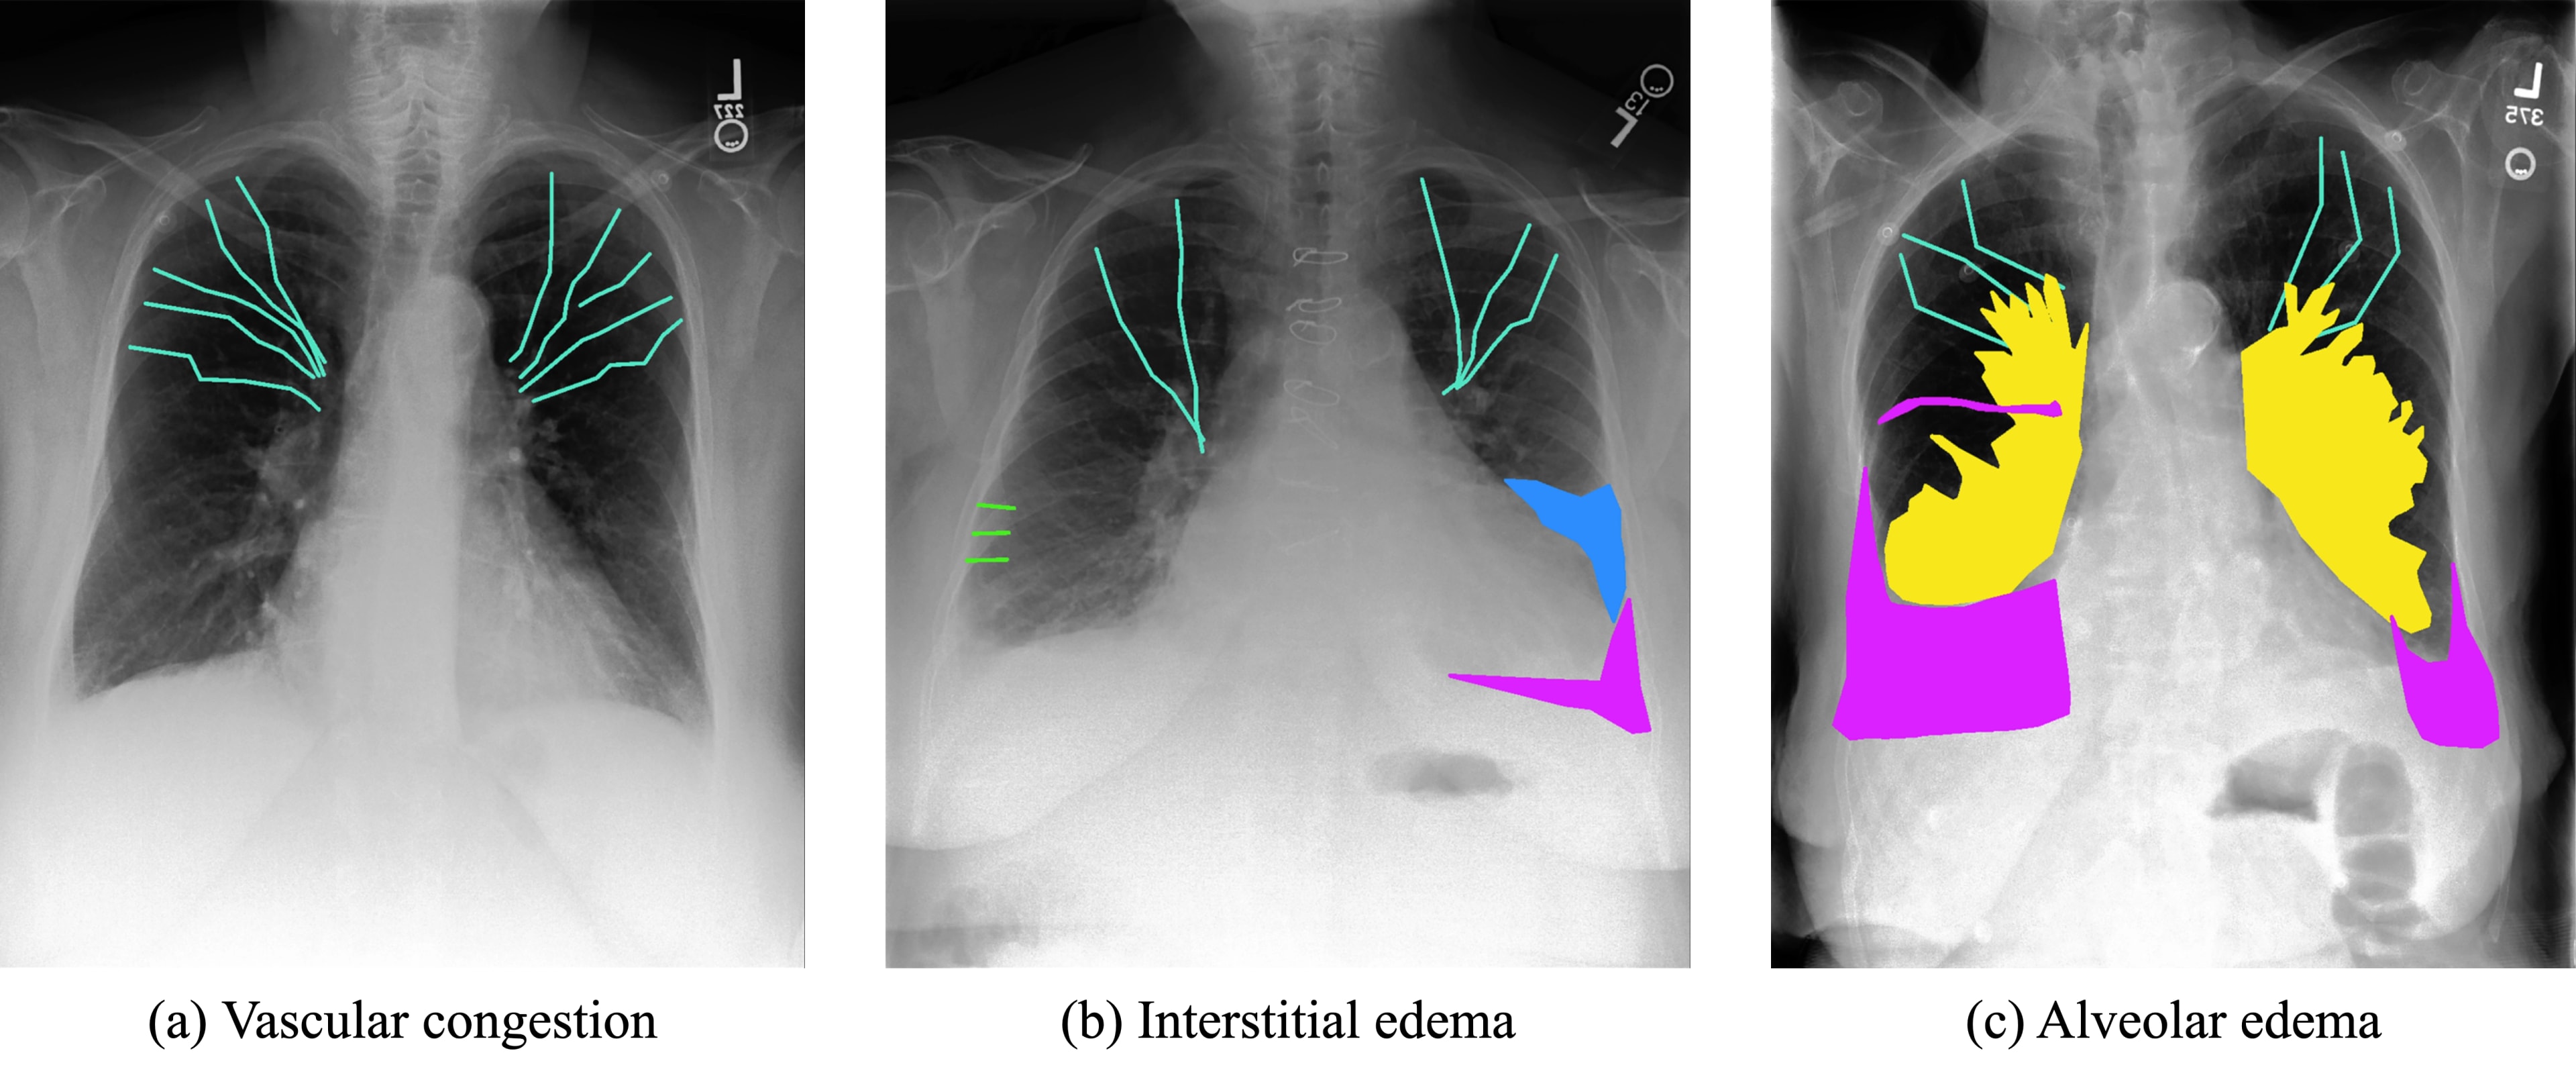

- •Annotation Method: Cephalization and Kerley lines were delineated using polylines; pleural effusion, bat wings, and infiltrates were marked with binary segmentation masks.

Radiological features such as cephalization, Kerley lines, pleural effusion, bat wings, and infiltrates were labeled by an experienced radiologist (Figure 1).